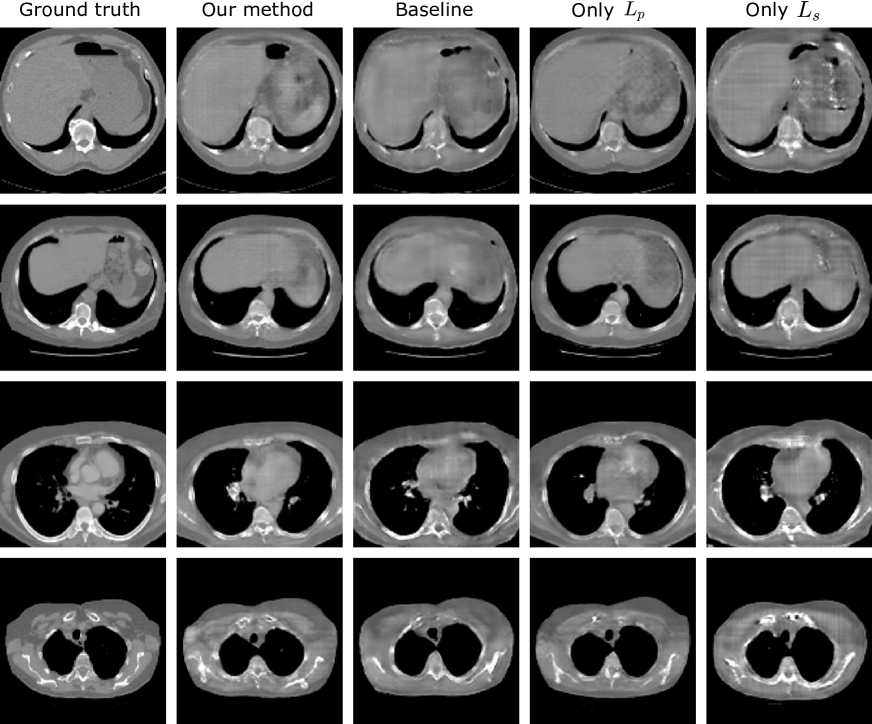

Refer to caption

Figure 2: Exemplary slices of the reconstructed CT volumes using the proposed and baseline method, in comparison with the ground truth.

Reconstruction performance

From the exemplary slices in Figure 2. The reconstructed CT volumes from the baseline method are ’visual real’ but only in terms of the body shape and regions with obvious contrast, such as the boundary of the lungs. However, the abdominal organs, for example liver, are not distinctive from the remainder regions. Some structural details, like the shape of vertebra, are also lost. The proposed method leads to the enhancement of such anatomical structural details and the organ contrast, while keeping the overall image quality. More specifically, the application of Lssubscript𝐿𝑠L_{s}decreases the image quality. It is expected as Lssubscript𝐿𝑠L_{s}only enhances the organ segmentation rather than the voxel-wise image quality. Regarding the anatomy, Lssubscript𝐿𝑠L_{s}contributes to organ-specific enhancement. As Lssubscript𝐿𝑠L_{s}in our experiments only targets for lung, liver and bones segmentation, the contrast of such organs in the reconstructed CT volumes are enhanced while there is no enhancement for other organs and structures. With Lpsubscript𝐿𝑝L_{p}the anatomical structures in the CT volumes are enhanced, such as the shape of vertebrae, and the contrast between adjacent anatomical structures, such as the boundary of the fat tissues. However, such anatomical improvements are barely indicated by the reconstruction metrics. Peak-signal-to-noise ratio (PSNR), structural similarity index (SSIM) and root mean squared error (RMSE) in the unit of Hounsfield unit (HU) are selected to evaluate the reconstruction performance. Table 1 shows the results of our proposed method in comparison with the baseline method. The proposed method leads to the improvement in the PSNR by 1.0% and the SSIM by 3.2%, and RMSE by 2.7%. With only Lssubscript𝐿𝑠L_{s}, the PSNR is deteriorated by 2.6%, SSIM by 3.2% and RMSE by 8.7%. The best improvement in metrics is obtained with only Lpsubscript𝐿𝑝L_{p}, the improvement is by PSNR 1.2%, SSIM by 3.2% and RMSE by 2.9%. From the reconstruction metrics, only Lpsubscript𝐿𝑝L_{p}can contribute to the improved image quality. The results from the ablation study are shown in Figure 4, higher λpsubscript𝜆𝑝\lambda_{p} can lead to higher PSNR and SSIM, indicating higher overall image quality. In contrast, higher λssubscript𝜆𝑠\lambda_{s} will not improve the overall image quality. The proposed method also results in higher PSNR and RMSE when λssubscript𝜆𝑠\lambda_{s} and λpsubscript𝜆𝑝\lambda_{p} increase, similar to the results with only Lpsubscript𝐿𝑝L_{p}.

Throughout our investigation, we have noted that the reconstructed volumes with enhanced anatomical structures can lead to inferior reconstruction metrics, i.e. PSNR, SSIM and RMSE. PSNR and RMSE are commonly used for the evaluation of reconstruction algorithms, and SSIM is originally designed for the assessment of digital image quality. Different from typical CT reconstruction methods, GAN-based methods depend on training a generator network to reconstruct the volumes from bi-planar projections, so such reconstruction is an ill-posed problem. During training the GANs, the network tends to reconstruct the CT volumes with bare or even no anatomical information, while maintaining high reconstruction metrics such as PSNR and SSIM. Some exemplary slices are shown in Figure 5. Therefore, in our research we also evaluate the organ segmentation of the CT volumes, based on the assumption that a network that is trained for organ segmentation can effectively evaluate anatomical structures.

Figure 5: Example slices that GANs fails to reconstruct anatomical structures in volumes. Column (a) is our proposed method with enhanced anatomical structures. (b) and (c) illustrate the CT reconstruction with deteriorated anatomical structure but high reconstruction metrics.